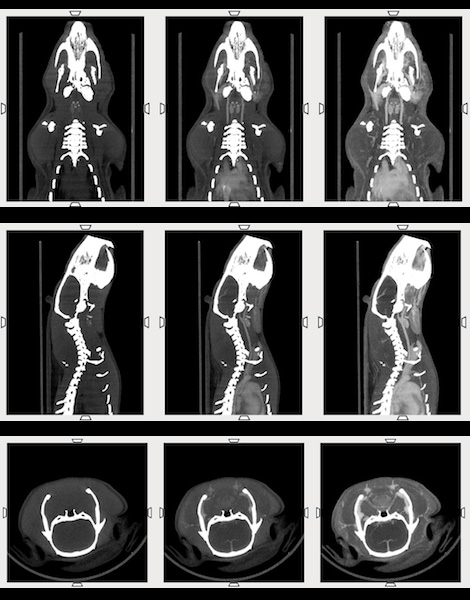

CASE 7: High workflow ex-vivo CT study of skeleton

workimg

• Courtesy of: S. Soussoko - Laetoli Productions / D. Brasse - IPHC CNRS Strasbourg

Research objective: Reconstitution of skeleton of Caribbean fruit bat

Animal model: Brachyphylla cavernarum. Dimensions: Skull length = 3 cm, Body length = 8.5 cm (incl. tail)

Acquisition protocol: 112 s acquisition time, 80 kVp, 1 mA, 1 bed position per plate, 6 acquisitions (complete skeleton), Total scan time < 12 min

Processing and reconstruction protocol: 0.06 mm isotropic voxel size